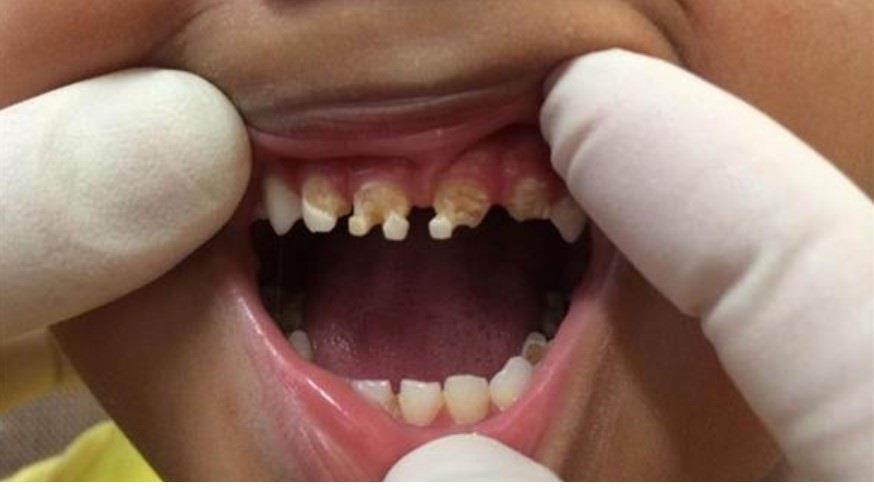

يترتب على إهمال تنظيف الأسنان عدة عواقب كضعف الأسنان وتشوهها، حيث تقوم البكتيريا بإنتاج أحماض تهاجم الأسنان وتؤدي إلى تكسرها وحدوث التسوس.